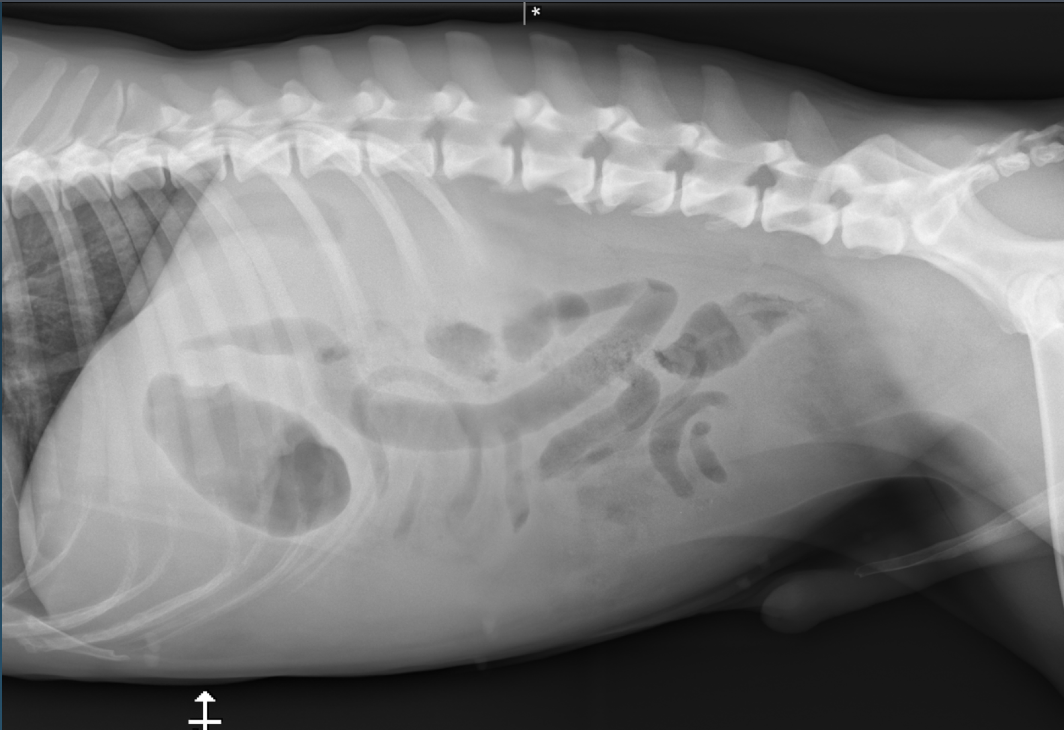

What is shown in these images?

normal abdomen and normal body wall in a dog